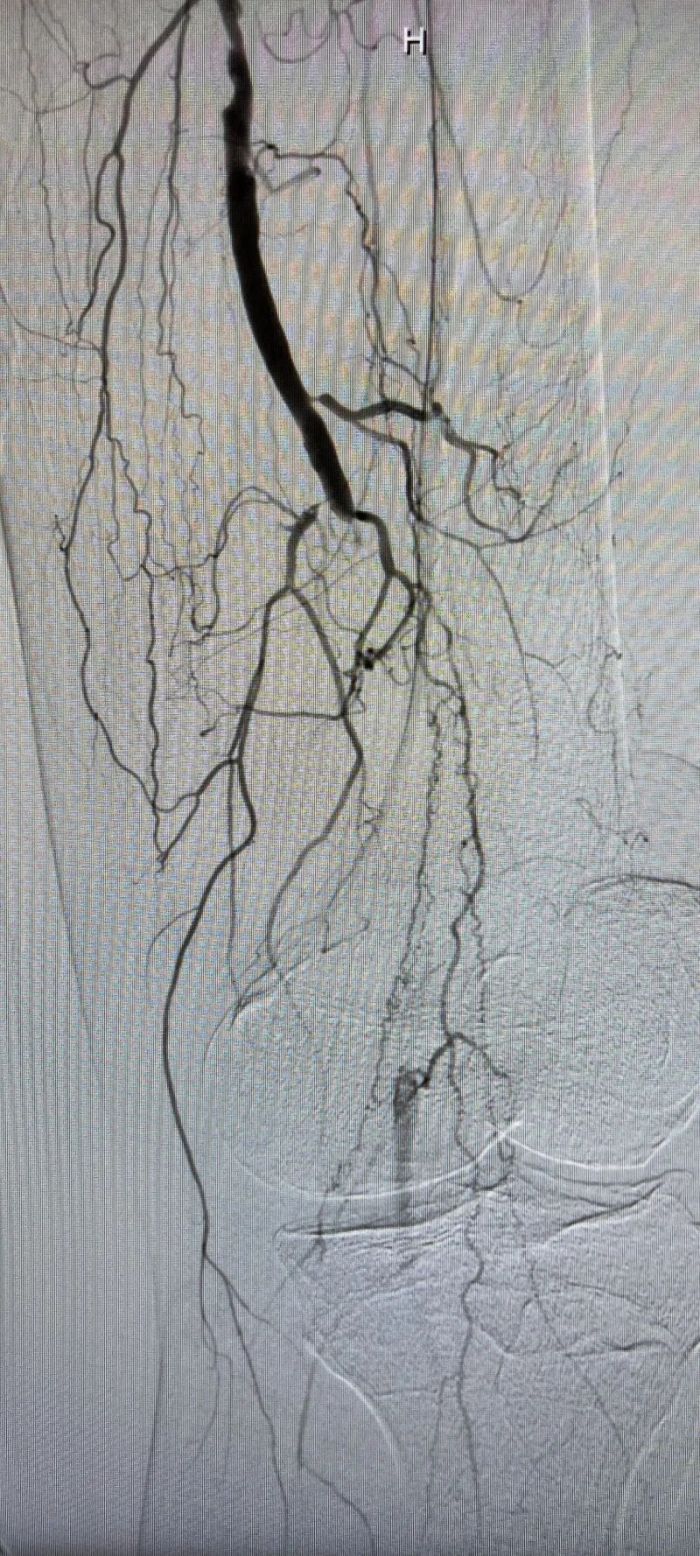

术前闭塞的腘动脉远端几无血流

球囊扩张后血管恢复通畅